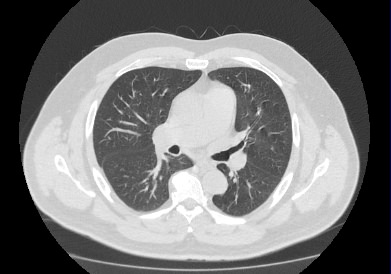

Информативность МСКТ органов грудной клетки дополняет функциональная проба, то есть методика проведения сканирования на вдохе (инспираторная КТ) и на выдохе (экспираторная КТ). При выполнении КТ на вдохе с задержкой дыхания удается добиться максимального контраста между наполненными воздухом легкими и более плотными структурами, такими как плевра, стенки бронхов и кровеносные сосуды. Кроме того, на фоне пневматизированных легких хорошо видны очаговые и диффузные патологические изменения.

При экспираторной пробе (пробе на выдохе) можно выявить воздушные ловушки (то есть стойкое повышение пневматизации легочной ткани) на фоне пневмонитов, бронхиолитов, обструктивных заболеваний легких, эмфиземы.